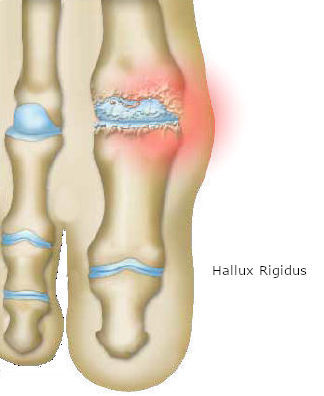

Η μαλακή επιφάνεια, που καλύπτει τα οστά (χόνδρος) στην άρθρωση του μεγάλου δακτύλου (μεταταρσοφαλαγγική άρθρωση) φθείρεται.

Οι άκρες του μεταταρσίου και της πρώτης φάλαγγας δεν ολισθαίνουν ομαλά μεταξύ τους.

Στην ιατρική γλώσσα, η πάθηση αυτή αναφέρεται ως hallux rigidus, που σημαίνει δύσκαμπτος μέγας δάκτυλος.

Το οστό χάνει την προστατευτική επιφάνεια του χόνδρου, λόγω της φθοράς. Τα οστά έρχονται σε άμεση επαφή και προκαλούνται τριβές κατά την κίνηση της άρθρωσης.

Όσο η ασθένεια εξελίσσεται, το οστό παραμορφώνεται. Στις άκρες του δημιουργούνται οστικές προεξοχές (οστεοποιήσεις ή οστεόφυτα).